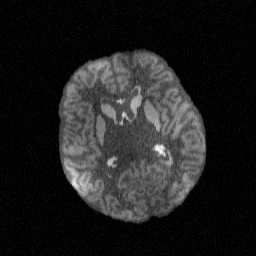

T1w(HF)T1w(LF)FLAIR(HF)Refer to captionRefer to captionRefer to captionRefer to captionRefer to captionRefer to captionRefer to captionRefer to captionRefer to captionRefer to captionRefer to captionRefer to captionRefer to captionRefer to captionRefer to captionInput(HF: high-field; LF: low-field)BrainFM featuresSCRATCH features

Figure 3: SCRATCH, well trained on high-field T1w scans with the same model architecture as BrainFM, produces highly descriptive features for high-field T1w images (1st1^{\text{st}} row), but does not preserve the same high quality useful for downstream tasks when handling low-field (2nd2^{\text{nd}} row) or other contrasts (3rd3^{\text{rd}} row).

We set the intra-subject samples within a mini-batch to have random contrasts and “mild-to-severe”, increasing level of corruptions (Fig. 2 (left)), to maximize the intra-subject variance while ensuring the stability of the training process against extreme corruption levels. As shown in Fig. 3, BrainFM obtains contrast/resolution-robustness that cannot be achieved by models trained from real images (due to the limited variability in their appearance), regardless of the backbone choices.